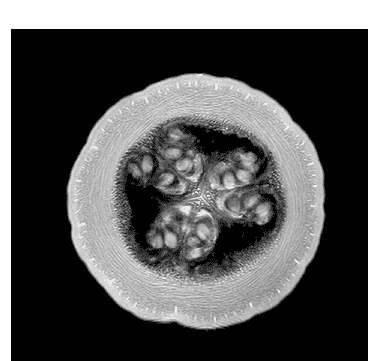

Quizás no sea lo más ortodoxo, pero no podemos negar su componente curioso y llamativo. Seguramente pocos nos imaginaríamos que una fruta de la pasión o la raíz de un apio tienen en su interior un aspecto muy similar al del cerebro. O que las fresas se parecen a un panal de miel. Aclaremos el misterio: esto ocurre cuando las frutas son observadas a través de una resonancia magnética.

Andy Ellison, técnico en resonancias magnéticas del Centro de Imágenes Biomédicas de la Escuela de Medicina de la Universidad de Boston, se ha propuesto enseñarnos de este modo cómo son las entrañas de las verduras y las frutas que comemos a diario. Para ello, ha utilizado la tecnología médica avanzada con la que trabaja para capturar las secciones transversales de estos alimentos, de la misma manera que cada día se hace con el cerebro humano, las rodillas o la columna.

El resultado, que recoge en su blog Inside Insides, son unas fascinantes imágenes y GIFs que nos muestran las frutas y las verduras desde otro punto de vista. Desde un interior tan llamativo y adictivo como lo pueden ser sus colores, formas y sus texturas. La colección es amplia y da para todo tipo de evocaciones, porque por el escáner de Ellison –en concreto, una Philips 3 Tesla MRI, explica– han pasado todo tipo de alimentos, desde los más comunes como las cebollas, los pimientos, los tomates o los plátanos, hasta lichis, la jaca (también conocida como jackfruit, uno de los frutos más grandes del mundo), la fruta del dragón o el kiwano (o pepino africano).